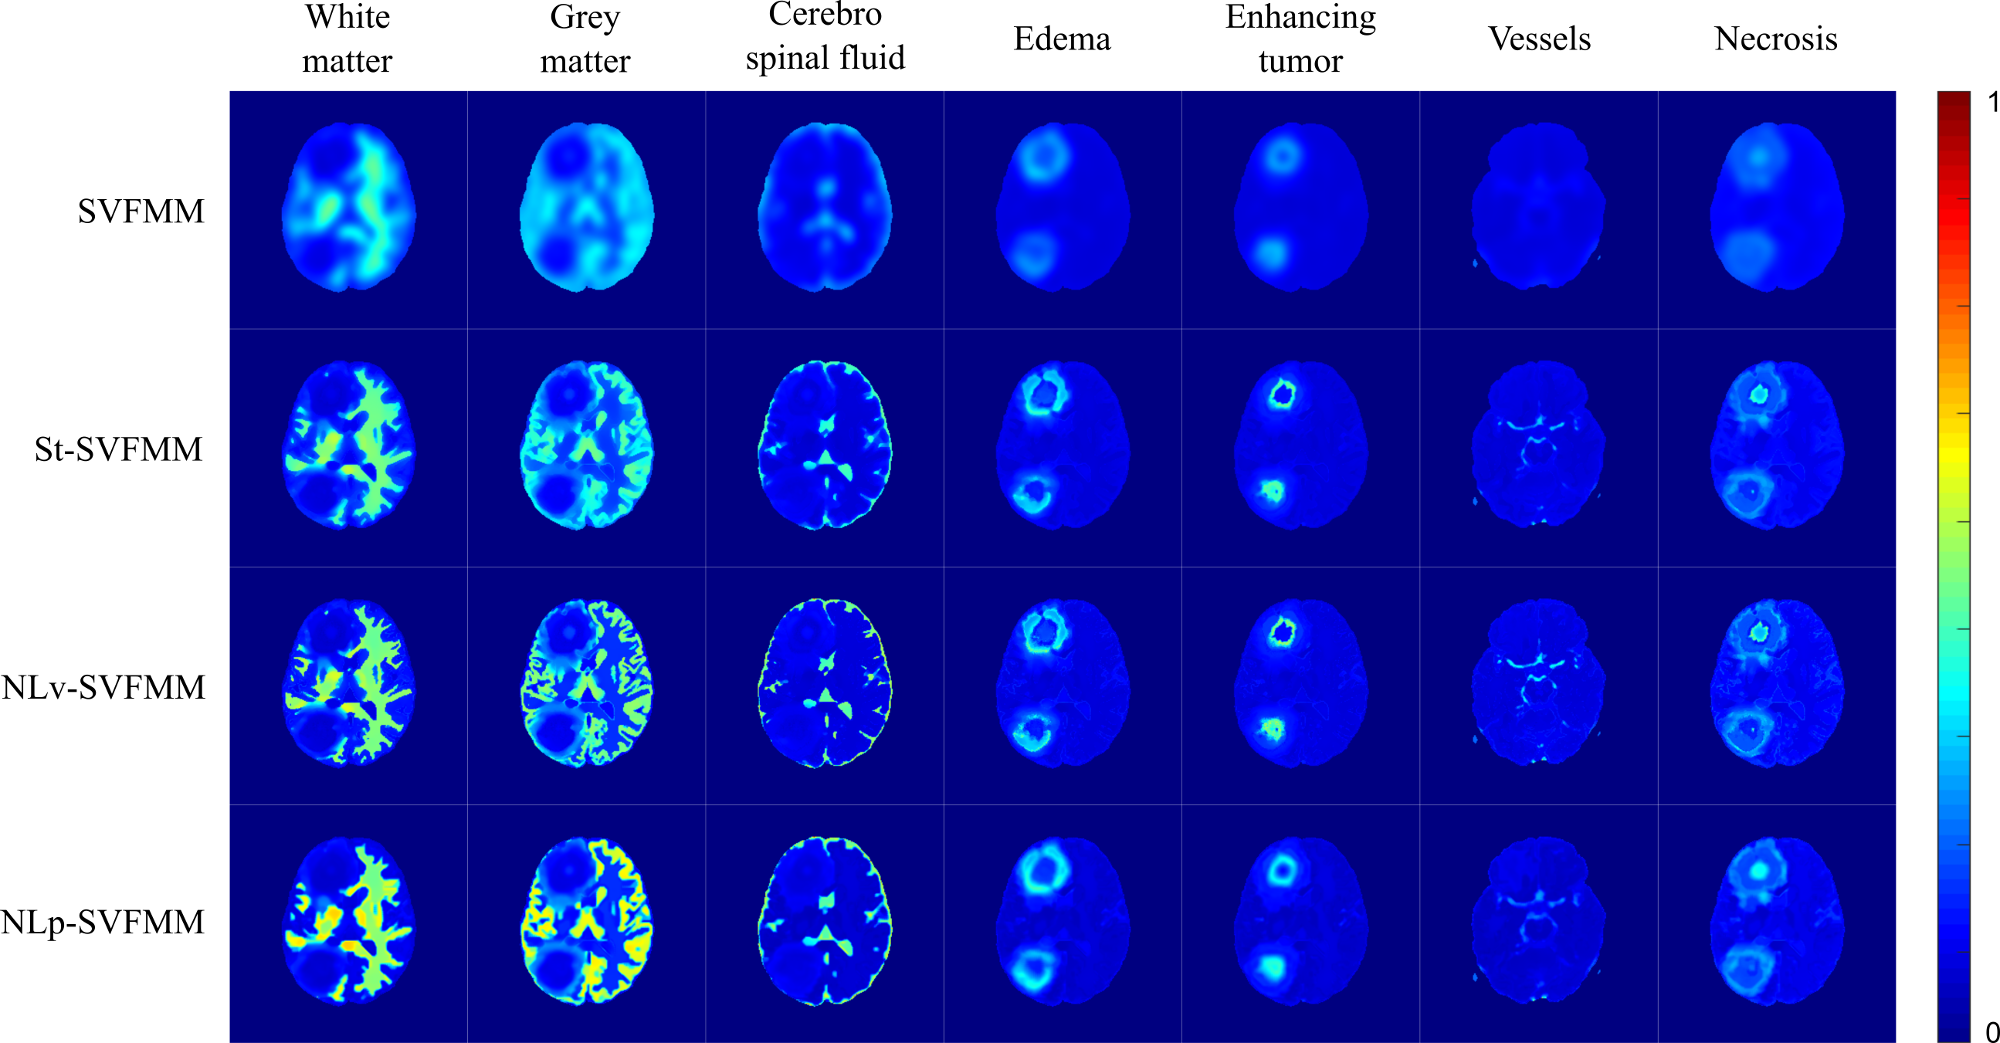

Comparative study of unsupervised learning algorithms for glioblastoma segmentation

In this study, a comparison of unsupervised learning algorithms, including structured and non-structured methods was performed for the task of high grade glioma segmentation. The study describes the statistical model underlying each algorithm and also proposes a general post-processing stage to identify which classes of an unsupervised segmentation correspond to pathological or healthy tissues. An independent evaluation of the performance of the unsupervised learning algorithms was carried out in a public real dataset, which demonstrated the capability of unsupervised learning to extract relevant knowledge from MRI data. This work was published in the journal contribution P1 (Juan-Albarracín et al, 2015b) and presented in the conference P2 (Juan-Albarracín et al, 2015a).

An unsupervised learning algorithm for structured prediction

A new variant of the Spatially Varying Finite Mixture Models (SVFMMs) family is proposed in this thesis. The algorithm, named Non Local Spatially Varying Finite Mixture Model (NLSVFMM), successfully merges the SVFMMs with the Non Local Means (NLM) framework, proposing a continuous Markov Random Field (MRF) that simultaneously enforces smooth constraints in homogeneous regions of the image while preserves the edges and structures without degradation. This approximation improves the existing approaches in terms of complexity of the model, as the NLM weighting function does not introduce additional parameters into the model to be estimated. Moreover, it outperforms current methods in terms of performance in a segmentation task of real world images. This work was published in the journal contribution P3 (Juan-Albarracín et al, 2019b).